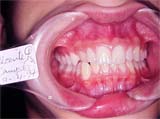

Fig. 3

Observamos a posição ectópica do elemento 13, e planejamos um aparelho expansor na maxila, com ênfase ao elemento palatinizado em conseqüência da mordida cruzada.